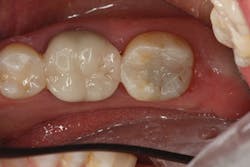

The difference in using this product over standard- or non-bulk-fill composites comes in the filling technique. The manufacturer states that you can predictably cure an increment of this composite up to 4 mm in depth. This assumes the light energy coming from your curing light is ideally positioned and is functioning properly (power intensity of 1000 mW/cm2 or greater). For carious lesions that are relatively small to moderate in size (figures 1a and 1b), this translates, in general, to being able to place one increment of composite that fills partway up the proximal box to the level of the contact and onto the occlusal pulpal floor (figure 2). The second increment could then be placed on top, which would fill the rest of the restoration.